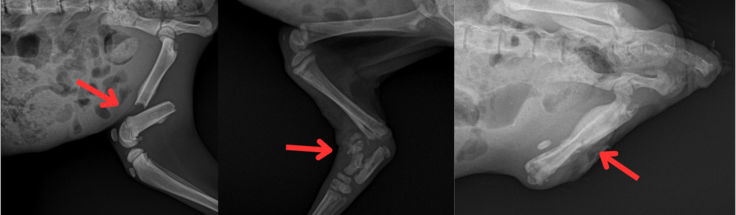

【レントゲン写真 左:はやて 中央:はやぶさ 右:のぞみ】

診察の結果、3頭のうち:

はやては骨折状態でしたが、感染はなく整復・固定による治療が可能と判断され、協力動物病院にて治療を実施。

一方、はやぶさとのぞみは、骨折部に感染が強く起きており、後ろ足の断脚手術が必要となりました。